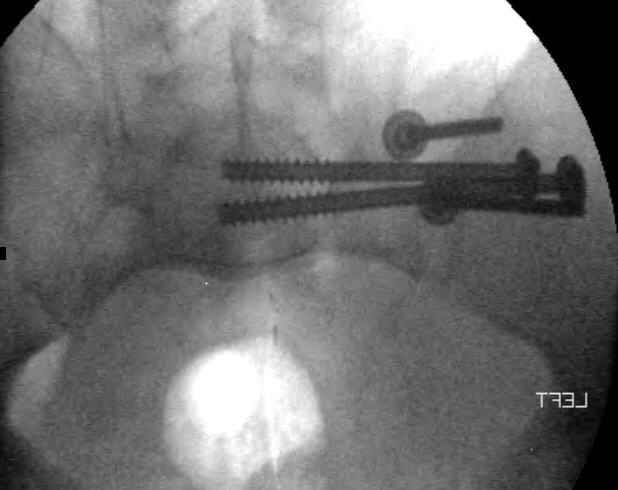

Hello gentlemen- Case is 52 YO male, fell out of treestand while deerhunting. He is 6 ft, approx. 260-275 lbs. Was hemodynamic unstable at local ER, sent to our Trauma center where circumferential pelvic binder placed and pt. stabilized with fluid, blood, and rewarming. Angiography not performed. An extraperitoneal bladder disruption was found, uro elected to treat non-operatively. Initial xray (not shown) demonstrated 5-7 cm wide at symphysis and SI joint. The first image attached is of CT once binder is in place. On post trauma day 5 the pt was taken to OR for ORIF of his iliac wing fracture and SI dislocation. The swelling/3rd spacing of fluid in the area of symphysis was profound, but quite acceptable posteriorly. Patient was prone for procedure, as I thought too difficult to fix the wing in lateral position. Of course the repair of wing was easy, but reduction of SI very demanding. The Floro images document the residual lack of reduction. That was the closest I could get it using 6mm joystick in wing, and clamp on sacrum and clamp through notch. The fixation was (initially) rigid. Anterior ex fix with supra-acetabular pins was placed due to condition of soft tissues, massive "beer-belly" overhanging the crest. Post trauma day ten patient's xray shows failure of posterior construct. Plan was to perform revision orif once soft tissues resolve considerably for full anrterior fixation and posterior fixation. However, while Im away for holiday (on Post trauma day 15), pt is developing septic clinical appearance, and trauma suspects pelvic abcess near symphysis and performs I and D - finds nothing but no primary closure performed. Posterior tissues/incision continue to look healthy. Now is post trauma day 17, pt is still tubed/on dopamine/and wbc still elevated, anterior incision still packed open. Clearly must get to bottom of possible sepsis, but then what? Thanks for you time - sorry for such lengthy clinical description. Thomas Schaller Kalamazoo, Michigan

Request for more images.. Axial and coronal recon (pt in binder.)

5. Your caudal iliosacral screw is/was in his spinal canal... it's low and posterior and the lateral fluoro image confirms this... a postop CT will show it (or it's trail at this point)... canal screws do not hold.